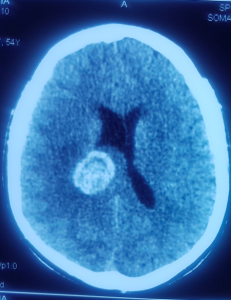

Pacienta noastră, doamna Toma, prezenta la internare tulburări de echilibru, de mers și de vedere, precum și deficit motor hemicorp drept și nu urmase decât un tratament operator pentru melanomul malign cutanat, fără un tratament oncologic adjuvant. Însă, după un examen RMN 3T cerebral (cu ajutorul unui aparat de ultimă generație RMN, singurul din țară, disponibil pentru toți pacienții în cadrul spitalului Sanador), și un examen CT la craniu (cu substanță de contrast), s-a stabilit diagnosticul de metastază cerebrală occipital stânga profundă, în vecinătatea unor structuri importante ale creierului (sistem ventricular, corpul calos etc.)

S-a reușit astfel îndepărtarea în totalitate a tumorii cerebrale, folosind cel mai modern microscop operator ”ZEISS KINEVO 900” (de asemenea, prezent în blocul operator al spitalului Sanador).

Tumoarea cerebrală a fost eliminată complet cu ajutorul intervenției chirurgicale

Doamna Toma și-a revenit imediat după ce efectul anesteziei a trecut. Aceasta a reușit să recupereze tulburările cu care se prezentase inițial la spital, după o zi petrecută la reanimare și alte patru zile de internare în cadrul secției de neuorchirugie. Examenele CT realizate după operație au indicat faptul că tumorăa a fost extirpată în totalitate, ceea ce confirmă faptul că operația a fost un real succes!